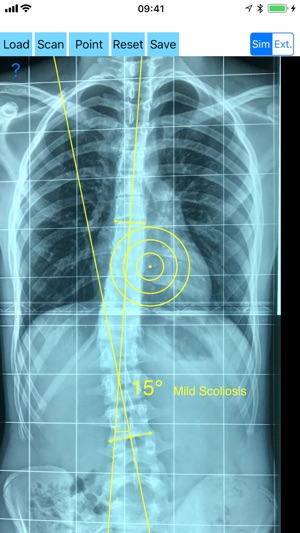

Cobb method is considered the standard for measuring curve size in scoliosis. Cobb angles are always measured from the superior end plate of the most cephalad end vertebra to the inferior end plate of the most caudal end vertebra in the curve. Meticulous line drawings and precise measurements is paramount importance in order to quantify the magnitude of spinal deformities and monitor the success or failure of treatment for scoliosis.

-Offers a very convenient way to determine the most accurate possibly way at once. By marking four points at the same X-ray, at each spine the App calculates the Cobb angle. In cases where values are out of normal ranges, the scoliosis is categorized according to measured angle as mild, moderate, severe. To simplify the process and to minimize inter-observer errors usually by not selecting the actual end vertebra, the app offers also in ext mode the ability to draw the vertical reference line through the patient’s sacrum and to identify more easily the end vertebrae s (ext method).

In a busy everyday practice, the examiner have to draw lines in X-rays or in clinical settings ,this it is time consuming and cumbersome. Accessory instruments like protractors, hinged goniometers, well sharp pencils, rulers or even transparent papers must be available. The app offers a very convenient and also accurate way to perform most common radiographic measurements for spine, in a blink of an eye in front of your screen. The build in feature of the app, allows results to be categorized may help decide what could be considered normal or pathologic.